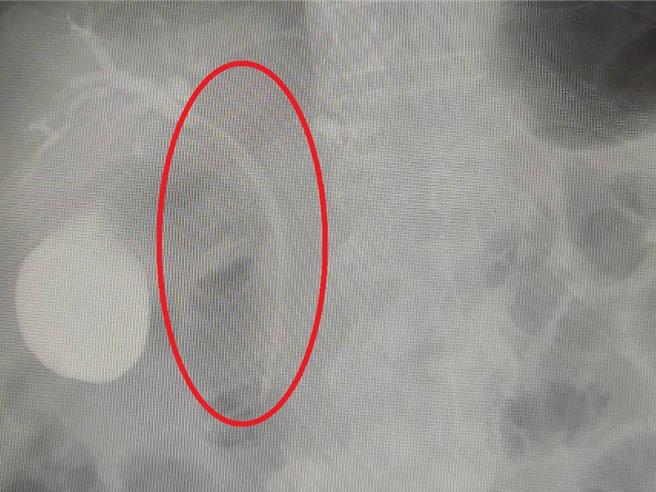

男子阻塞的胆管,经医师进行胆道支架置入术(红圈处)后,顺利改善黄疸问题。(大千医院提供/李京升苗栗传真)

苗栗县71岁老翁是B型肝炎病人,因最近出现右上腹间歇性钝痛、食欲不佳、粪便呈轻度黏稠状、茶色尿液、及全身外观逐渐变黄等症状,而到医院就医,经检查发现其胆管被疑似肿瘤的物体阻塞住,导致引起黄疸问题。医师以内视镜逆行性胰胆管摄影术,进行胆道支架置入术,顺利改善黄疸状况后,病人进一步接受手术治疗,经切片确认为慢性胆管炎合併相关硬化性胆管炎,后续顺利恢復并持续于门诊追踪。